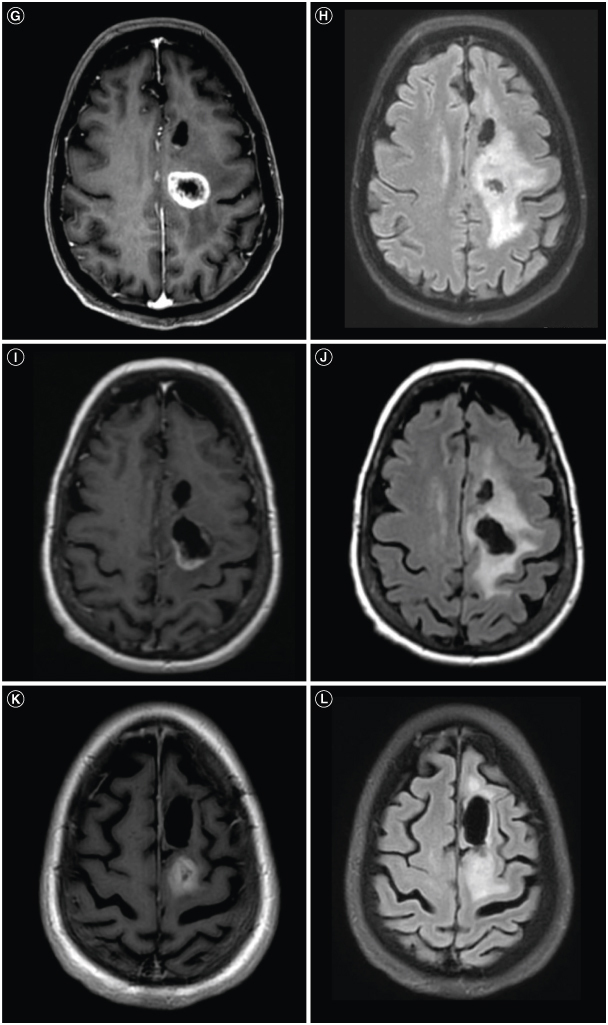

Glioblastoma is the most common malignant primary brain tumor. Despite its infiltrative nature, extra-cranial glioblastoma metastases are rare. We present a case of a 63-year-old woman with metastatic glioblastoma in the lungs. Sarcomatous histology, a reported risk factor for disseminated disease, was found. Genomic alterations of TP53 mutation, TERT mutation, PTEN mutation, and +7/-10 were also uncovered. Early evidence suggests these molecular aberrations are common in metastatic glioblastoma. Treatment with third-line lenvatinib resulted in a mixed response. This case contributes to the growing body of evidence for the role of genomic alterations in predictive risk in metastatic glioblastoma. There remains an unmet need for treatment of metastatic glioblastoma.

Abstract Image